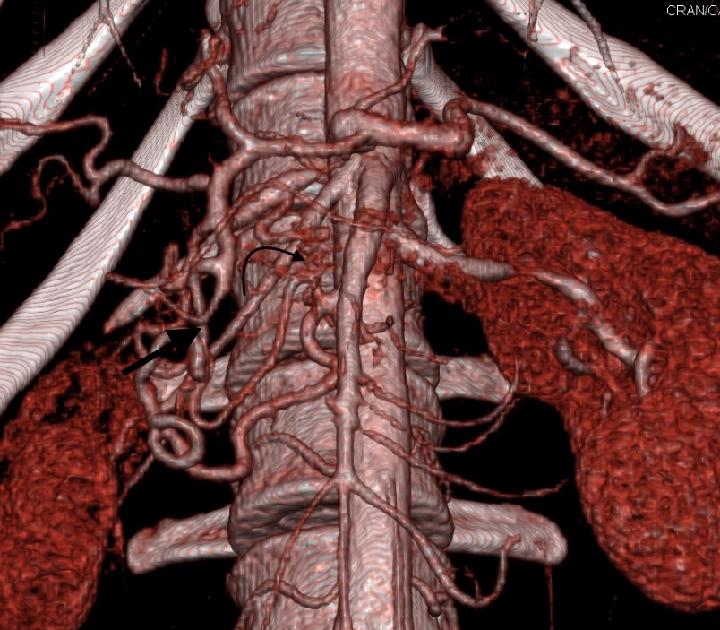

Suprapatellar lesion

35 yo male with vague knee pain since 2 weeks. There is a suprapatellar lesion. Do you have an idea what could it be? Fluid with septa and thickened synovium? Hematoma? PDfs, T1W and T2W images are obtained. Additionally partially torn ACL was depicted.

0 likes • Aug 13